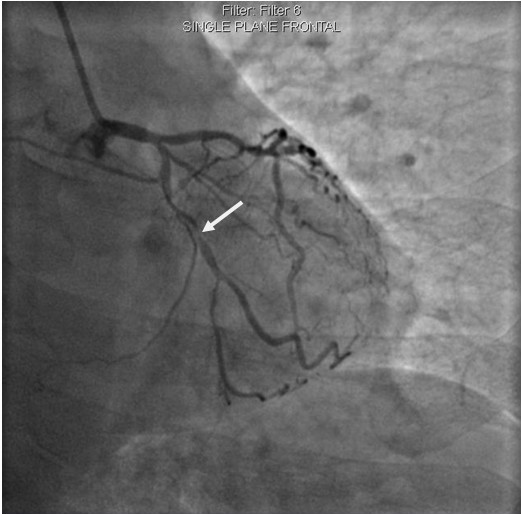

術前,翟光耀主任還親自為李先生復查冠狀動脈造影,造影結果顯示:患者的前降支、回旋支、右冠等冠脈三支嚴重病變、嚴重鈣化,且均為彌漫性長病變,最重處99%以上管腔極嚴重狹窄。翟主任仔細閱讀造影結果后指出:結合李先生的實際情況,雖然微創介入手術難度比較大,但仍可行;李先生心臟三支主干動脈均存在極其嚴重的狹窄,每一支動脈均至少植入2-3枚支架,根據患者的耐受情況,李先生可能需要分3次分別對三支動脈進行介入手術;考慮到李先生路途遙遠,病情嚴重,不宜反復奔波,并且患者迫切要求能夠徹 底解決病痛,在病情允許的情況下,如果手術順利,爭取為患者進行“一站式”手術,一 次 性解決全部三支動脈病變!

手術方案確定之后,在心血管內三科趙景新主任、介入醫學科富孝晨主任的配合下,翟光耀主任親自擔任主刀,分別依次對李先生的三支動脈進行了完全血運重建。由于手術進展順利,李先生術中沒有任何癥狀,耐受良好,于是成功的將三支動脈“一站式”治療!術中,由于李先生左主干遠端分叉處存在嚴重病變,翟光耀主任選擇國際指南推薦的DK-mini-Crush技術,確保了分叉處兩支主干開口均萬無一失。據悉,DK-mini-Crush技術是目前冠脈分叉病變領域最為復雜及難以掌握的介入技術之一,對手術醫生經驗、體力均提出了極大的挑戰。極為擅長復雜介入技術的翟光耀主任卻用嫻熟的技術確保了李先生手術的成功。